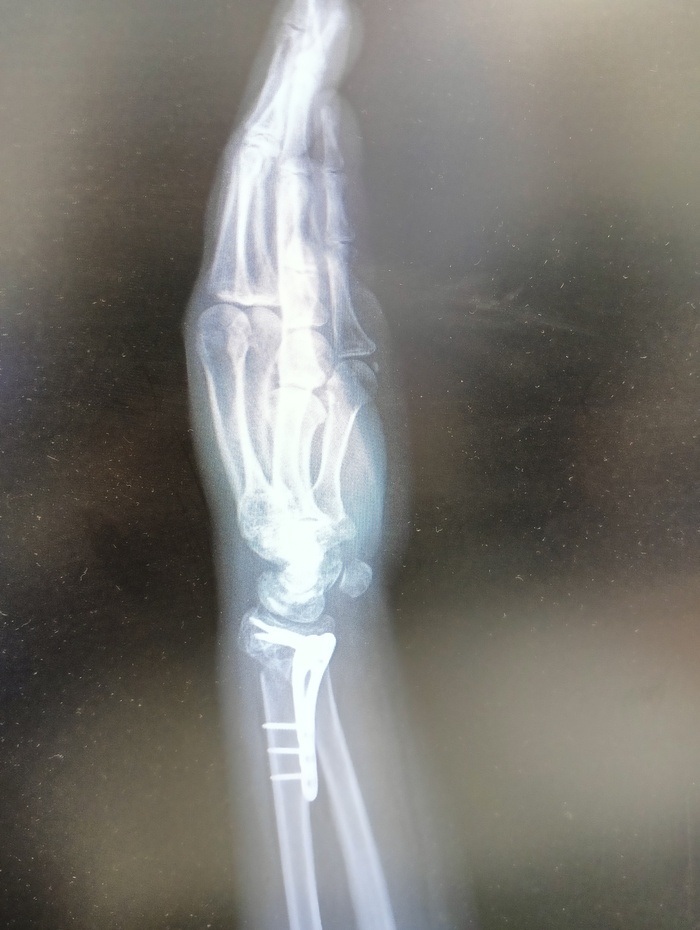

22 июля я неудачно упала и получила оскольчатый перелом дистального метафиза лучевой кости со смещением отломков более чем на 1/2 ширины диафиза. Открытый перелом шиловидного отростка локтевой кости. Была месяц в гипсе, но ничего не срослось. Диастаз костных отломков стал до 4 мм. Локтевая ушла в сторону на 5 мм. На 3 месяц после перелома мне сделали операцию, поставив титановую пластину. Сегодня сделала ренген и получила вот такой результат: Застарелый сомнительно консолидирующийся перелом дистального метафиза правой лучевой кости в условиях накостного МОС. Помимо отрыва шилообразного отростка локтевой кости, видно, имеется разрыв дистального радио-ульнарного сочленения.

Как я понимаю, Шиловидный отросток не прирос и стал болтаться, травмировав ткани внутри... Возможно, что это от реабилитации, я прохожу maps терапию для разработки руки, а может и просто, ведь рукой стараюсь пользоваться.

в ччетверг еду к хирургу, который меня оперировал. Но очень интересно мнение. Нужна ли тут операция и какая...

верхние ффото через 2 месяца после перелома, потом после операции и 2 нижние - сегодня